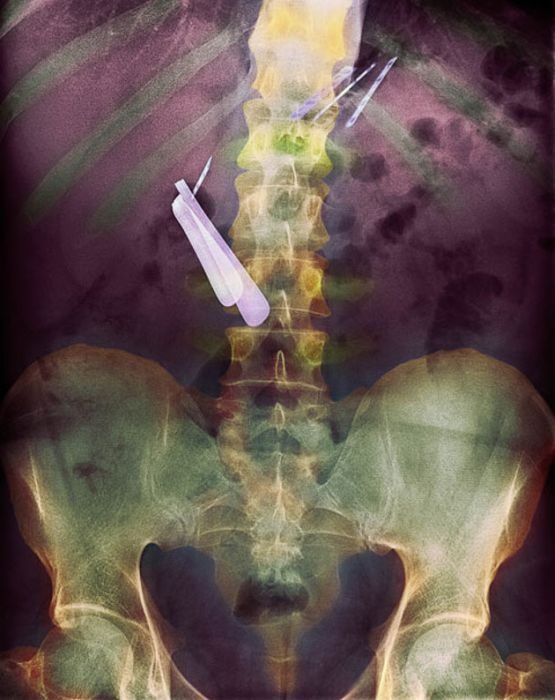

Задница — не самый лучший футляр для очков